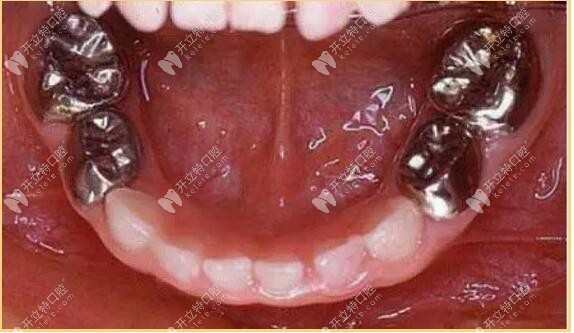

二、金屬預(yù)成冠

又叫不銹鋼冠,常用語乳牙磨牙治療,兒童不銹鋼乳牙欲成歡是一個(gè)預(yù)先塑性的、與牙齒貼合度比較高的金屬牙冠,用來套在乳牙上,保護(hù)牙齒并加強(qiáng)牙齒的強(qiáng)度,確保正常被恒壓替換。

金屬預(yù)成冠

金屬預(yù)成冠能有效防止充填物的脫落、繼發(fā)齲的產(chǎn)生和牙體組織的折裂,保證兒童的頜骨生長和繼承恒壓的替換。